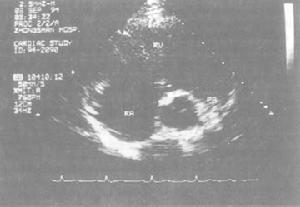

(4)心臟病變右心室肥大、室壁增厚、心腔擴張、肺動脈圓錐膨隆、心肌纖維有肥大和萎縮等改變,間質水腫,灶型壞死,壞死灶後為纖維組織所替代。部分患者可合併冠狀動脈粥樣硬化性病變。

(6)胸部X線及心電圖:X線早期表現肺紋理增多,肺氣腫時為肺野透光度增強,橫膈下降,胸廓增大,肋骨上抬,側位呈前後徑增大。隨著病情的發展,可出現肺動脈段凸出,右心室增大。心電圖表現為:右心肥厚、肺性P波。

肺心病的診斷主要靠病史及臨床表現,結合體徵、心電圖、X線等檢查。心電圖發現右心室肥厚,肺性P波和X線胸片顯示右心室增大是診斷本病重要依據。